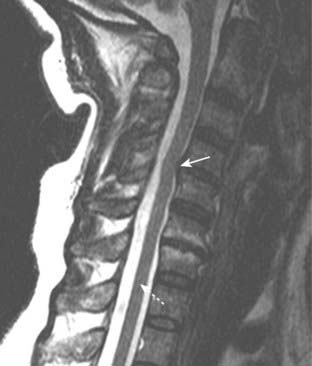

image In the cervical spine, disk herniations occur most frequently at C4-C5, C5-C6, and C6-C7 (Fig. 24-5).

Figure 24-5 Herniated disk, C4-C5 on MRI.

The spinal cord is dark (dotted white arrow) relative to the high intensity (whiter) signal surrounding it which is the cerebrospinal fluid in the spinal canal. A herniated disk (solid white arrow) extends posteriorly from the C4-C5 disk space and compresses the cord.